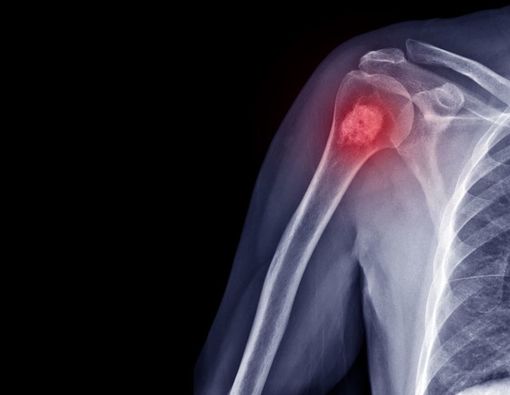

Dokter Dyah Novita Anggraini menjelaskan bahwa limb salvage adalah prosedur menghilangkan tumor di area limb, yakni pada lengan atau kaki.

Prosedur limb salvage biasanya dilakukan untuk mengatasi chondrosarcoma, yaitu jenis kanker yang menyerang tungkai kaki dan lengan.

Limb salvage tergolong menjadi salah satu metode bedah yang rumit, mengingat chondrosarcoma merupakan jenis kanker ganas karena terbentuk di tulang rawan.